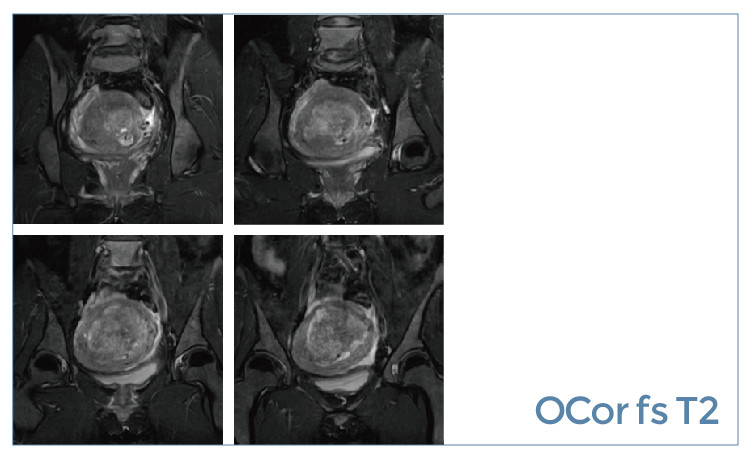

【朗润影像档案】磁共振影像病例分享(编号20190621)